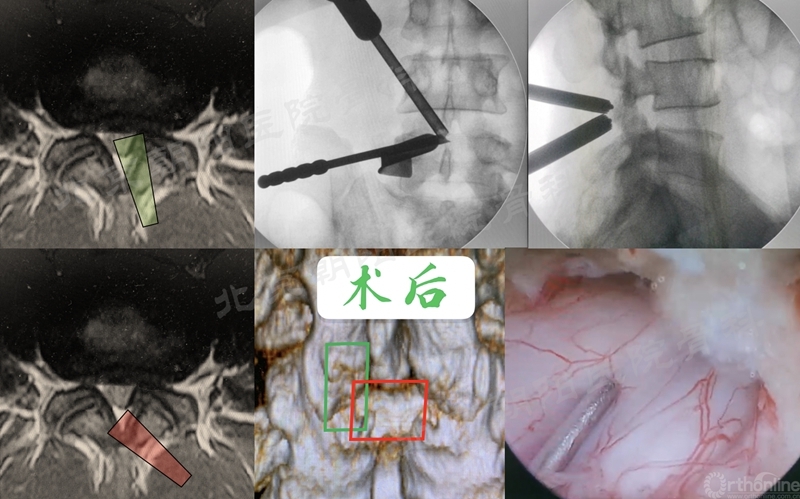

在经历15例UBE减压手术的学习曲线后,本团队进行了UBE腰椎减压融合术:#16例UBE,L4/5 LSS。

UBE-LIF手术步骤大致按常规开放手术:

1、显露L4椎板下缘-L4/5关节突-L5椎板上缘;

2、Kerrison钳减压L4下关节突(全部去除)-L5椎板上缘-L5上关节内侧缘(尽量靠外)-黄韧带整体切除;

3、硬膜外止血,显露椎间盘,确定椎间隙位置和方向;

4、椎间隙处理:骨刀,髓核钳,终板刮刀,Kerrison钳,电凝,+耐心;

5、自体骨+同种异体骨植骨;

6、可撑开融合器植入(透视定位);

7、检查遗漏的骨块,彻底清除神经周围的致压物;

8、必要时做对侧黄韧带减压;

9、经皮植入椎弓根螺钉,加压固定。

术前MRI和术中定位

椎间隙处理

植入可撑开Cage

术后X线片与CT(矢状面)

术前、术后MRI及CT(轴位)